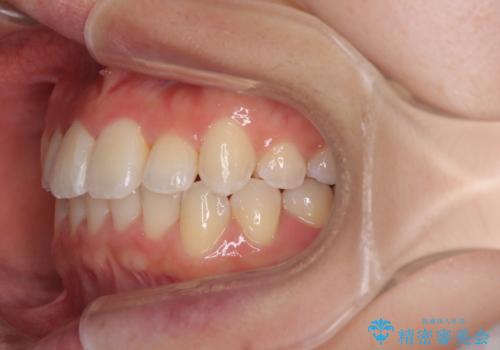

前歯のクロスバイト 裏側に隠れた歯をワイヤー装置で短期間治療

- 上顎前歯のクロスバイトを気にして来院された患者様です。

ワイヤー矯正でもマウスピース矯正でも対応可能でしたが、マウスピースによる自己管理に一切の自信がないとのことで、ワイヤー装置にて矯正治療を行うこととしました。

装置の外見を気にしていましたが、短期間で治療を終えることができるだろうと伝えると、安価であるメタルブラケットを選択されました。

想定通り、1年強で綺麗に仕上げることができました。